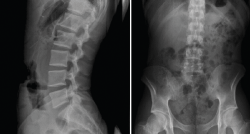

Radiografía simple de columna lumbar

Los estudios radiológicos simples son fáciles de obtener, están al alcance de la mayoría de los médicos y centros asistenciales, y son económicamente asequibles, sobre todo en comparación con otras técnicas diagnósticas. Como consecuencia de ello, teniendo en cuenta la elevada incidencia de dolor lumbar, es considerado el síntoma que determina con mayor frecuencia la solicitud de radiografías entre los pacientes no ingresados. Sin embargo, las diferentes revisiones sobre el tema y la opinión de los expertos en la materia abogan por limitar su uso a pacientes concretos y a un pequeño número de proyecciones(19).

En pacientes con un proceso doloroso lumbar, solo en un bajo porcentaje de casos, entre el 25 y el 30%, los estudios radiológicos son normales. Esto ya lo objetivó Nachemson(20), quien comprobó que solo en 1 de cada 2.500 radiografías de la columna vertebral dorsolumbar de pacientes adultos aparecían hallazgos de valor diagnóstico no sospechados clínicamente.

La excesiva valoración de la utilidad real de los estudios radiológicos en el dolor lumbar y la actitud defensiva que frecuentemente se adopta en un intento por evitar cometer errores diagnósticos se enfrentan con el objetivo de limitar, en la medida de lo posible, la realización de exploraciones complementarias innecesarias, además de no someter al paciente a radiaciones ionizantes excesivas e inadecuadas(3,21).

Como consecuencia de esto, es necesario conocer los criterios que deben seguirse para realizar el diagnóstico diferencial de los síndromes radiculares y de las patologías específicas más frecuentes con dolor lumbar (según el algoritmo de las Figuras 3 y 4), así como para protocolizar la solicitud de estudios radiológicos en pacientes con dolor lumbar (Tablas 3 y 4).

Figura 5. Espondiloartropatía degenerativa.

Otros hallazgos radiológicos frecuentes, como las anomalías congénitas de transición lumbosacra, espondilolistesis, secuelas de epifisitis, la espina bífida oculta, las escoliosis leves o moderadas, la hiperlordosis, espondiloartropatía, etc., se encuentran casi por igual en pacientes con y sin dolor lumbar (Figuras 5, 6 y 7)(22,23).

Debe resaltarse que, en los casos de dolor lumbar atendidos en la mutuas de accidentes laborales, debido a las especiales características de la atención sanitaria que realizan y a la necesidad de determinar desde el primer momento la contingencia del proceso, es imprescindible realizar siempre al menos una radiografía anteroposterior (AP) y lateral (L) en bipedestación (o carga) de la columna lumbar.

Proyecciones radiológicas

La más frecuentemente utilizadas son la proyección AP y L. Se debe procurar incluir al menos hasta T11 y el borde superior de las caderas (Figura 8).